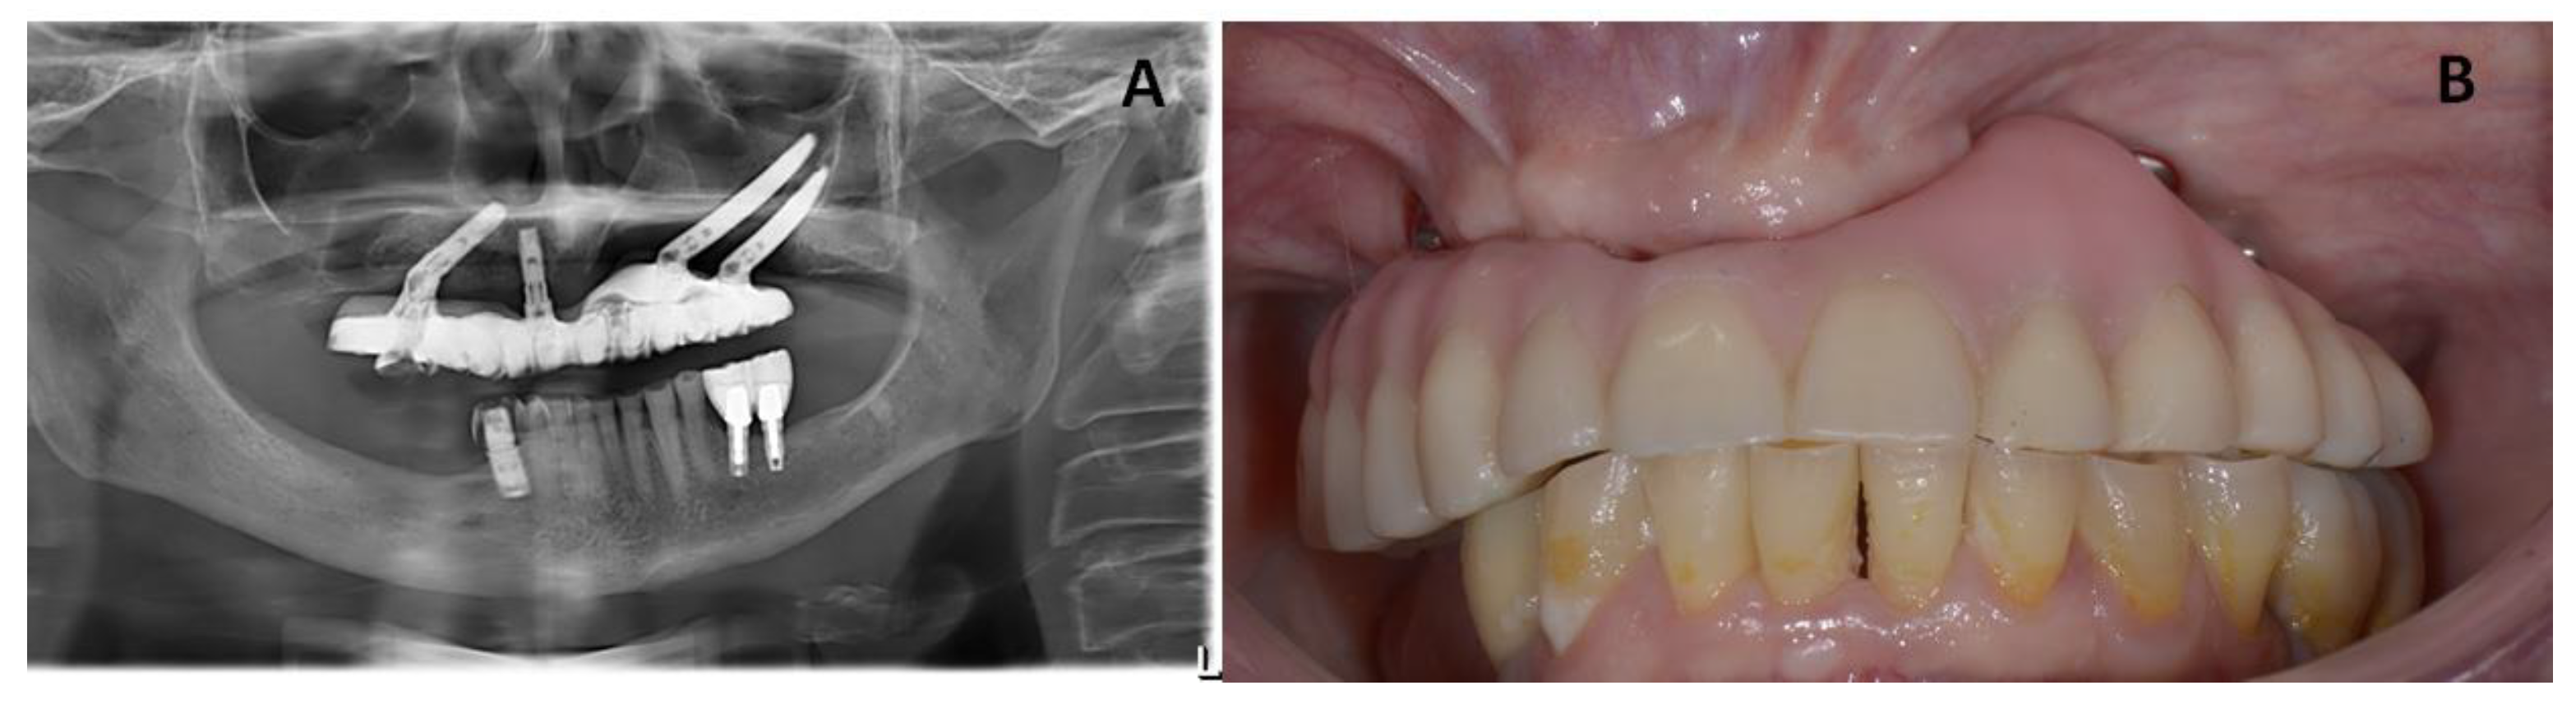

February 2017: The patient received additional surgery that included the debridement of the bone sequestrum and removal of the implant at #21. After removal of the anterior dental implant, the patient did not receive any fixed maxillary prosthesis. At this point, a removable provisional prosthesis with soft lining material was delivered to monitor the healing period. A fixed prosthesis was planned, with two additional zygomatic implants as anchorage, in case of complete relief from the symptoms of MRONJ.

After total healing was achieved with no complications and no further signs of relapse of the MRONJ lesion, two zygomatic implants were inserted in May 2017. The zygomatic implants used in this study were Zygomatic Noris ® (Noris Medical Ltd., Nesher, Israel) with sizes of 45 mm (REF: NM-F4445) and 35 mm (REF: NM-F4435) in length and 3.5/4.2 mm in diameter, with 45° angled multi-unit abutments (Figure 4).

In the first follow-up appointment after one month, the patient exhibited healthy oral tissues with no signs of complications. A final Toronto prosthesis was delivered at six months after implant insertion (Figure 5).

Figure 5. (A) Radiographic images from the patient showing healing of the MRONJ lesions with two zygomatic implants inserted after one month of follow-up. (B) Clinical images from the patient showing healing of the MRONJ lesions with two zygomatic implants inserted. (C) Intra-oral view showing the final prosthesis.